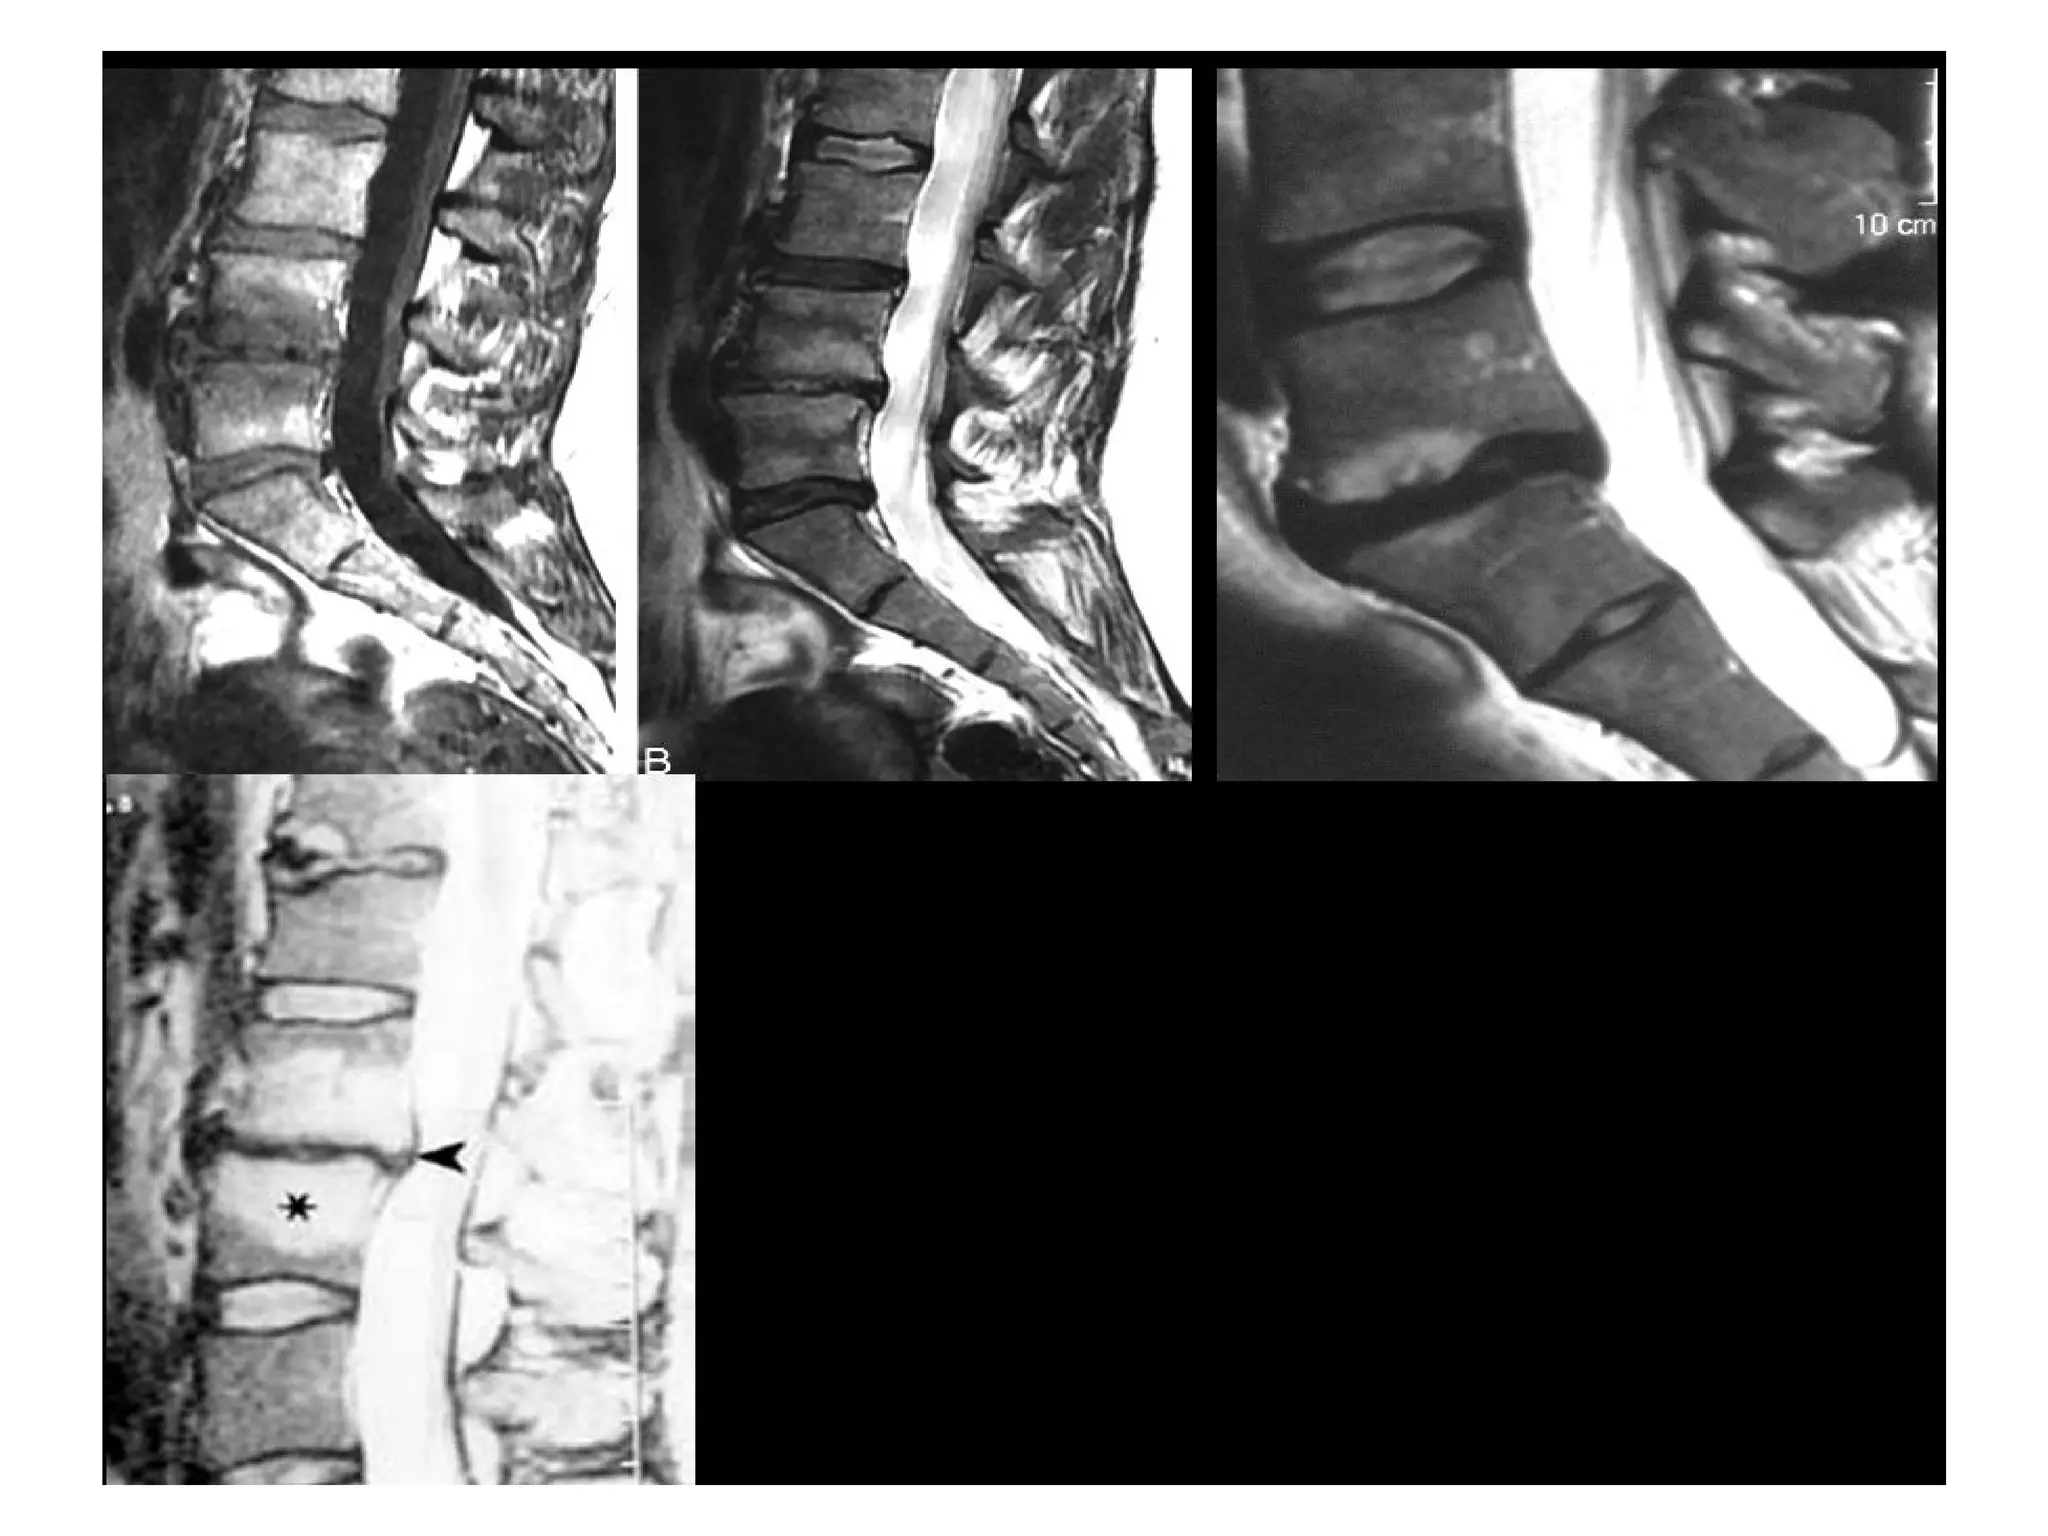

Modic type 1 deg. changes (MI)

Hypointense on T1WI (A)

Hyperintense on T2WI (B)

Modic changes

type 1 in

lower endplate

of L4

and

upper endplate

of L5

Modic Type I (Edema)

Described as disruption and fissuring of the endplate

with regions of degeneration, regeneration, and

vascular granulation tissue.

Modic type 2 degenerative

changes (MII)

hyperintense on T1WI (A)

isointense or slightly hyperintense on T2WI (B)

type 2 in the

the upper

endplate of S1

Modic type 3 degenerative changes

(MIII)

Hypointense on both

T1WI (A) and T2WI (B)